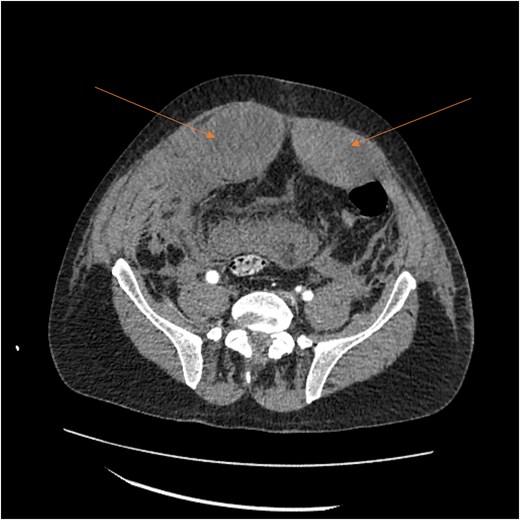

Laboratory results showed thrombocytopenia and erythrocytosis, with a hemoglobin level of 18.6 g/dl and platelets at 840 00/μl. A CT scan of the abdomen and pelvis was ordered to rule out malignancy or paraneoplastic syndrome causing the VTE (Fig. 1). The CT showed no lesions suspicious for malignancy but revealed a left RSH, managed conservatively.